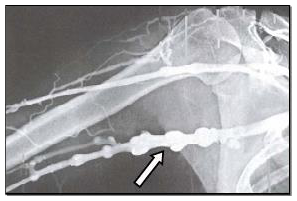

Observe a radiografia abaixo, que inclui a articulação do ombro, na porção indicada pela seta.

Observa-se pelo contraste, na porção indicada, um segmento de

A

veia.

B

artéria.

C

nervo.

D

gânglio.

E

ducto linfático.